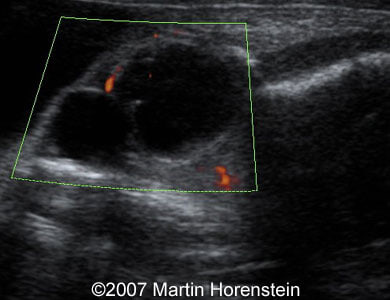

Dacryocystocele Martin Horenstein, MD. Article Published: Mar 30, 2007 Argentina These are some 2D and 3D images of congenital dacryocystocele. Images 1 and 2: 2D gray scale (image 1) and color Doppler (image 2) images showing cystic structure medially to the right ocular bulb representing dacryocystocele. Images 3 and 4: 3D images showing dacryocystocele medially to the right eye of the fetus. Â Discussion Board Start a discussion about this article Add to Favorites Favorite